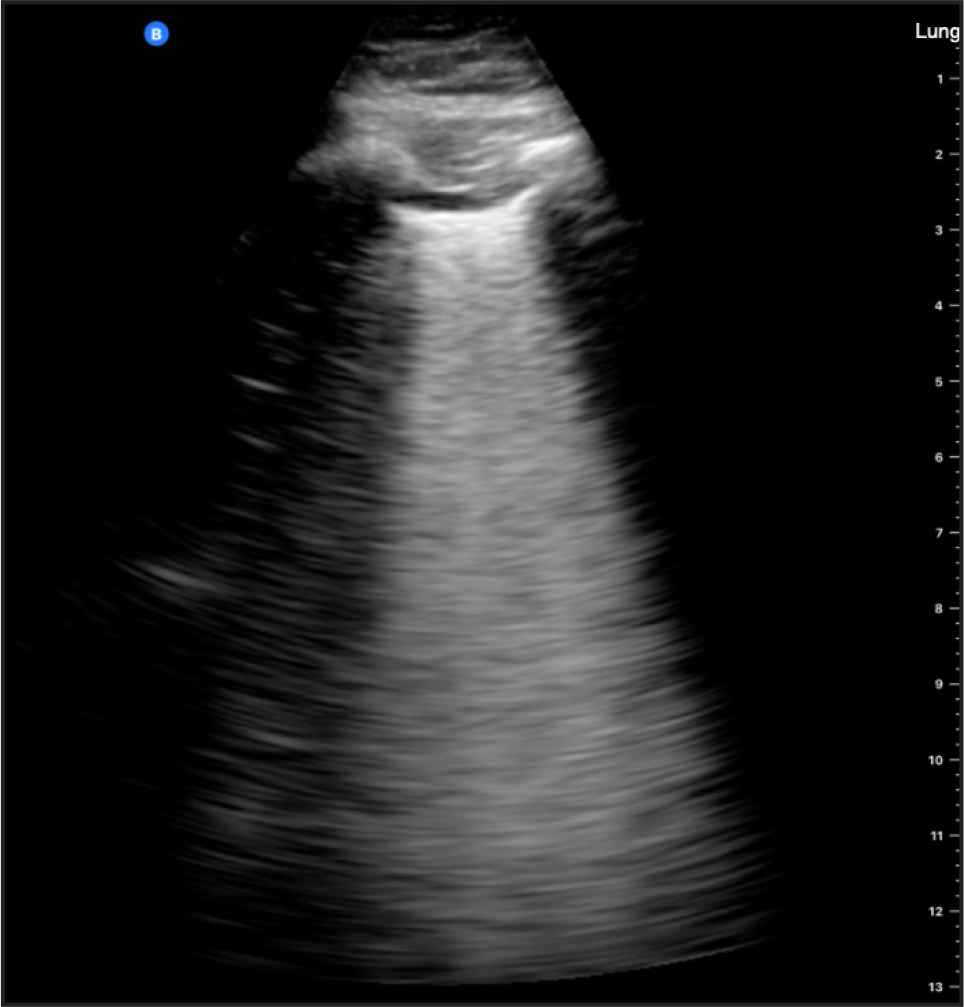

The light beam artifact was detected in 11 patients, nine of whom had COVID-19 (Figure 4). The difference in proportions was statistically significant (p = 0.024). The results diagnostically achieved 81.8% (95% CI, 48.2–97.7%) sensitivity, 75.0% (95% CI, 34.9–96.8%) specificity, 82% (95% CI, 56.7–93.9%) positive predictive value, 75.0% (95% CI, 44.6–91.8%) negative predictive value, and an overall accuracy of 78.9% (95% CI, 54.4–93.9%).

Light beam artifact detected in a 51-year-old male with COVID-19 (positive RT-PCR).

The light beam artifact was originally hypothesized to reflect a patchy localization of COVID-19 pneumonia. It has been specifically described as “a shining band-form artifact spreading down from a large portion of a regular pleural line, often appearing and disappearing with an on–off effect in the context of a normal A-line lung pattern visible in the background” [11]. It is thought to represent an early sign for viral spread in the peripheral lung corresponding with the ground-glass opacifications detected on CT. However, few researchers argue the specificity of the light beam artifact to COVID-19, claiming that it is simply “a patchy area of white lung” [34]. In contrast, our data showed that it had a high diagnostic yield as a typical LUS feature of COVID-19 and can be reliably detected using a handheld ultrasound device. Indeed, our results correspond to Volpicelli et al.’s [33] findings that suggested its value as an independent predictor of RT-PCR positivity.

As with all ultrasound artifacts, the light beam artifact can be influenced by the probe orientation, machine settings, and probe type. We recommend using a convex profile probe operating at low frequency (<3 MHz) with the focus positioned at the pleural line for accurate interpretation. Notwithstanding, our results support the role of the light beam artifact as a more sensitive and specific pattern compared to conventional patterns in LUS. This positive finding agrees with a few published case reports and observations [11,13,35]. Our study is the first to systematically analyze this artifact in an observational study on COVID-19. An international multicenter research is currently ongoing to investigate the specificity to particular COVID-19 phenotypes [11,35].